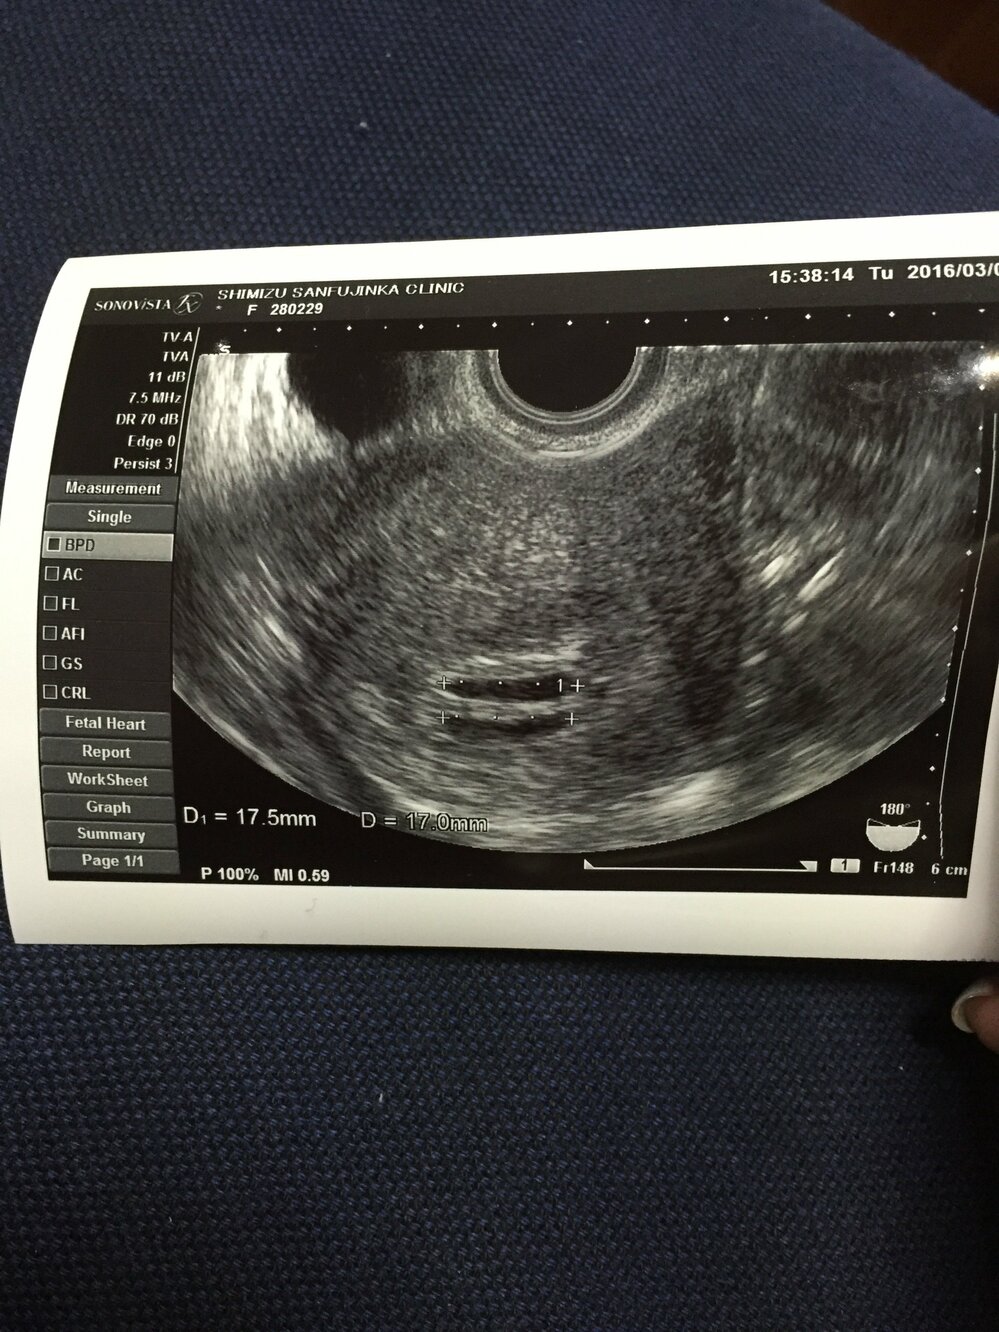

2卵生双子エコー写真

21年2月28日 7週 エコー 双子 投稿者 に未分類 に未分類 この時、妊娠2ヶ月。 私はいわゆる二卵生の双子で 「二絨毛膜二羊膜」でしたので早くからわかったのだと思います。 人生の転機です。 ※二絨毛膜二羊膜(にじゅうもうまくにようまく)とは 胎盤も二つ、部屋も二つで分かれています。 双子の中で一番そこで、今回は備忘録も兼ねて双子のエコー写真を公開しようと思います。 双子の妊娠や出産、育樹などに興味のない方にとっては、なんの価値もないかもしれませんが、双子のママにこれからなる方の参考になればと思います。 目次 1 双子の妊娠が判明したのはこのエコー写真でした! 2 10